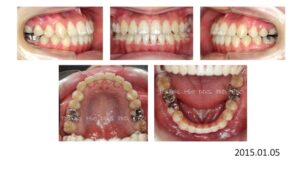

検査、診断の結果、この患者さんは矯正のみで治療することは不可能、上下顎骨の離断が必要で外科矯正となりました。

この患者さんも歯が入らないから、顎を拡げましょうと言われ拡大を続けましたが、治療前の状態をみると、判断を誤っていることがわかります。